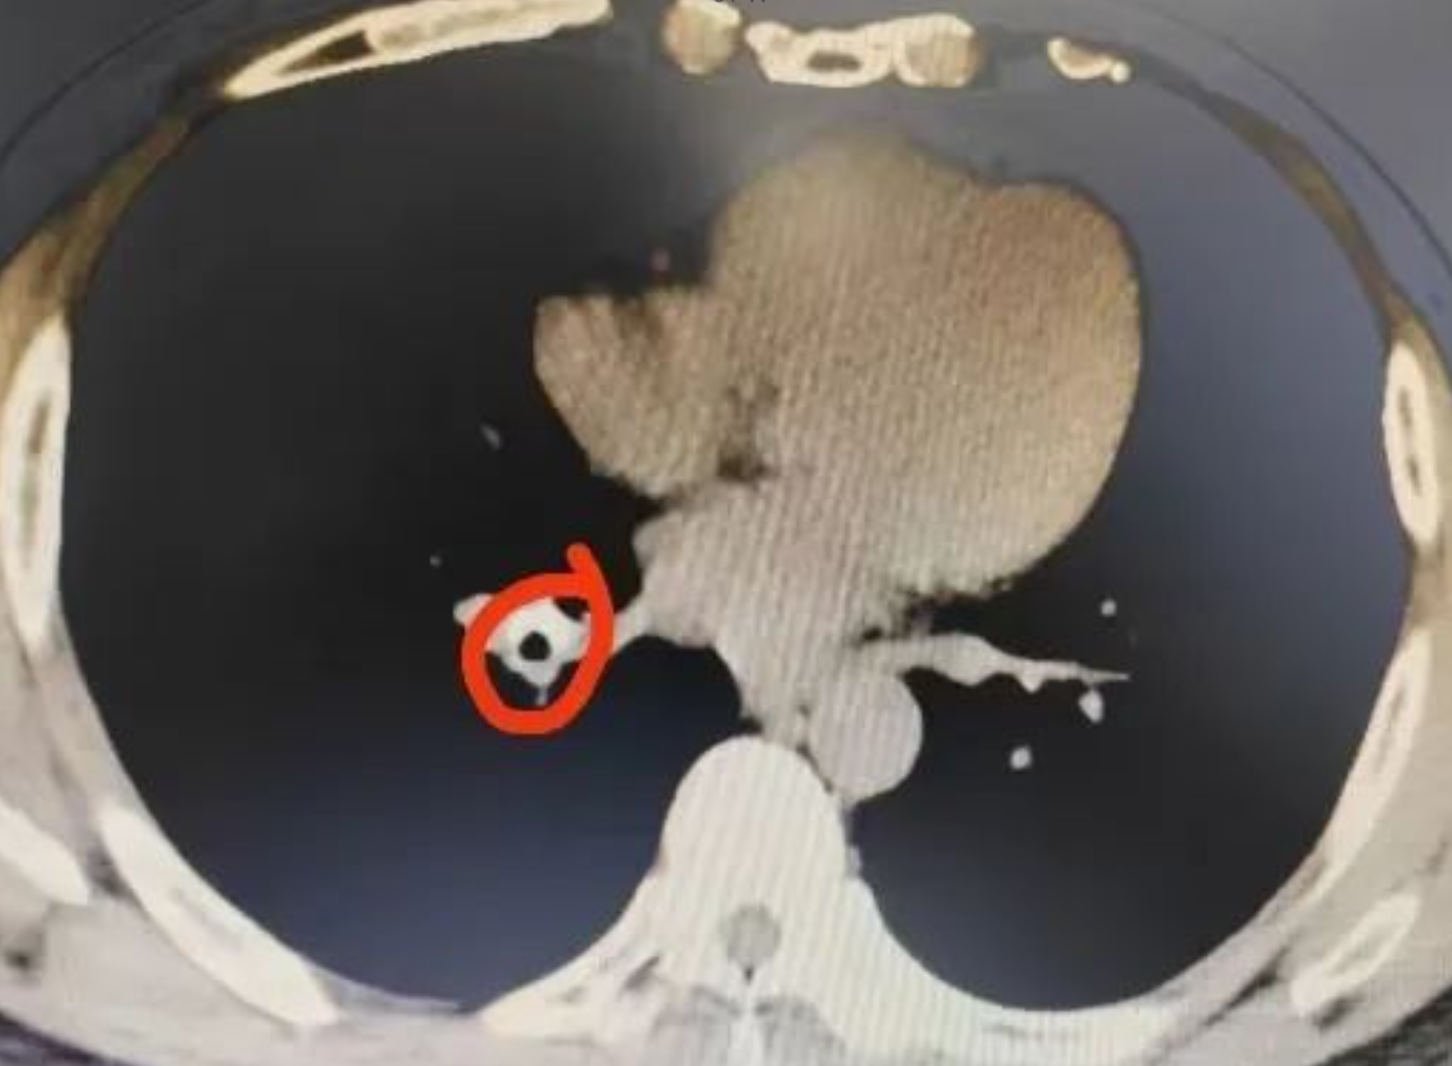

內媒報道,49歲的鍾先生今年8月到廣東省第二人民醫院東莞醫院就診,原因是他數年前開始出現反覆胸悶,但一直被當作肺炎去治療,雖然有所好轉,但過一段時間又發作。經CT檢查,鐘先生右肺下葉支氣管竟然發現有異物,周圍粘膜組織增生,一碰就出血。經過支氣管鏡手術,大小約1.3厘米X0.8厘米的異物被順利夾出,竟是半粒花生。鐘先生回憶,原來大概八、九年前,他一次喝酒食花生時突然嗆咳,當時也沒在意,但自此之後就經常咳嗽,這才是導致鐘先生反覆不適的罪魁禍首。